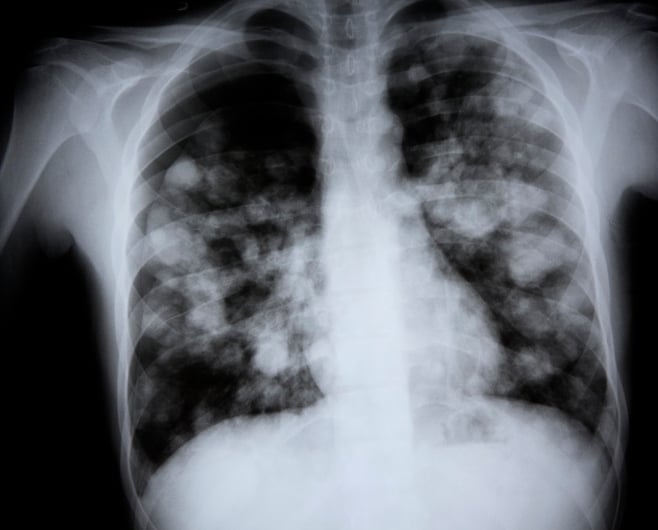

Most x-ray images are electronically stored digital files. At Stanford we take extra precautions to minimize our patients exposure to radiation including using. On a chest x-ray the ribs and spine will absorb much of the radiation and appear white or light gray on the image.

Different parts of the body contain different tissues which vary in how much X-ray radiation they absorb depending on how dense they are. Radiation exposure is known to damage the cells that were exposed and can lead to cancer. The radiation exposure of an adjacent newborn the radiographer and other persons in the room was simulated using phantoms during X-ray examination of the chest using vertical and horizontal beams.

Imaging should only be used if there is a definite medical benefit. Radiographic exposure of neonates attracts particular interest because of their greater cell. A chest x-ray for example delivers 01 mSv while a chest CT delivers 7 mSv see the table 70 times as much.